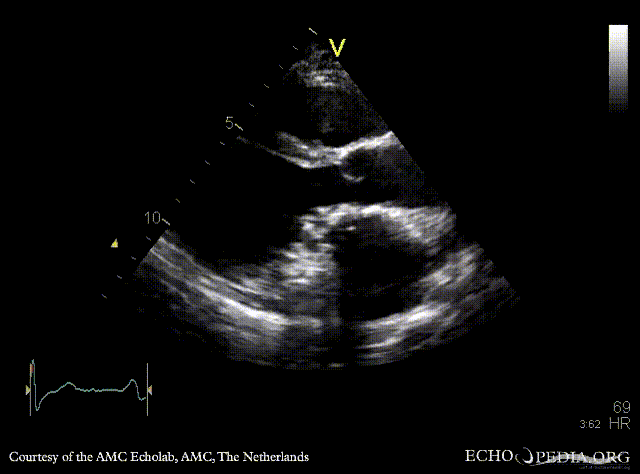

E00598.gif E00599.gif

A4CH A2CH